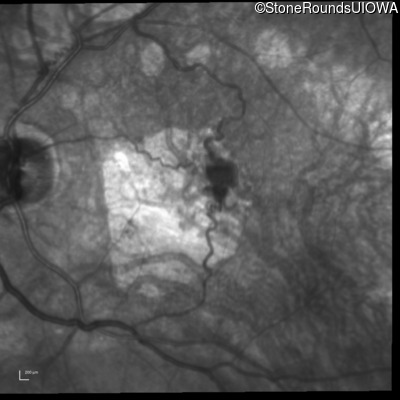

Infrared Fundus Photograph - Right - 20/125 -2

Exemplar

Infrared Fundus Photograph - Left - 20/80